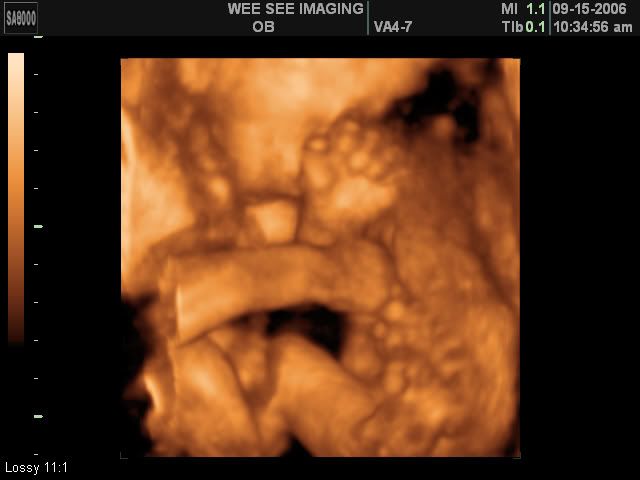

Victoria Rose Kelly

Date Due: December 15, 2006